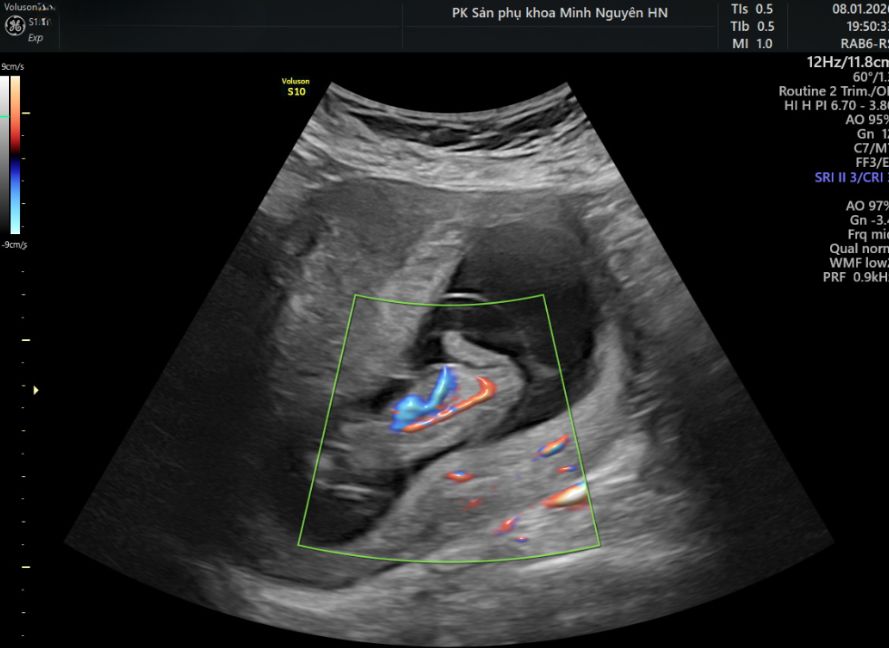

Siêu âm chẩn đoán dây rốn một động mạch như thế nào?

Siêu âm sẽ đếm số mạch trong mặt cắt ngang dây rốn. Sau đó kiểm tra mạch máu hai bên bàng quang thai. Nếu chỉ thấy mạch ở một bên, đây là dấu hiệu đặc trưng.

Tuy nhiên, có thể xảy ra nhầm lẫn nếu hai động mạch dính nhau ở đoạn gần bánh nhau. Dây rốn xoắn nhiều cũng làm việc đếm mạch khó hơn. Vì vậy, siêu âm rà soát lại ở nhiều vị trí là bước quan trọng.